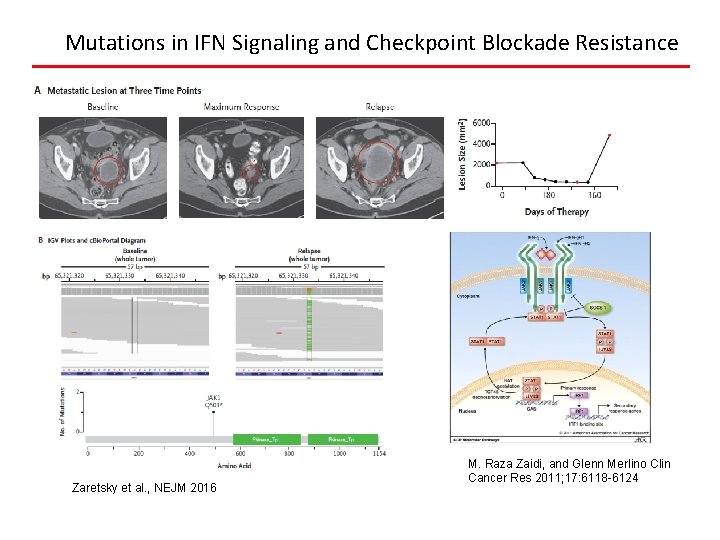

Mutations in IFN Signaling and Checkpoint Blockade Resistance Zaretsky et al. , NEJM 2016 M. Raza Zaidi, and Glenn Merlino Clin Cancer Res 2011; 17: 6118 -6124